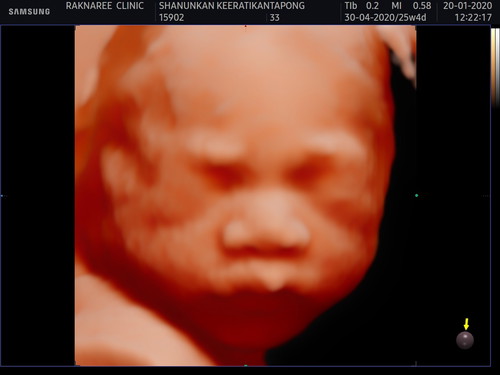

ซาวน์ 4 มิติ 25week เพศหญิง